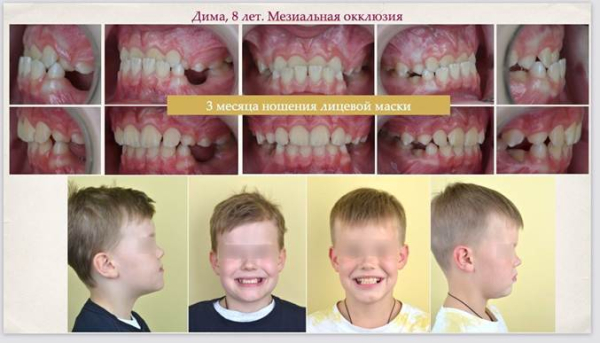

Дима пришёл к нам с мезиальной окклюзией: при улыбке нижние зубы перекрывали верхние. Это появляется рано, лет в пять-шесть, и это очень плохо, потому что нижняя челюсть буквально блокирует рост верхней.

Для Димы мы выбрали комбинированный метод. Первое — это нёбный расширитель. Такой аппарат с опорой на молочные зубы называется аппарат Хааса. Дима сам выбрал скин Спанч Боба. А второе — съёмная лицевая маска. Это такое специальное устройство, которое, грубо говоря, надевается на лицо и фиксируется на лбу и подбородке. У аппарата есть небольшие крючки — к ним крепятся резинки, которые соединяют его с маской. Это нужно, чтобы челюсть постепенно двигалась вперёд.

Да, это выглядит как стальной экзоскелет. Носить его ребёнок должен максимальное количество часов в сутки, но в школу, естественно, его не надевают — только дома.

Всего за три месяца мы получили полное нормальное перекрытие и новую улыбку.

Возраст восемь лет — идеальный для такого лечения. Если бы родители Димы решили повременить, то лет в 20 его ждала бы челюстно-лицевая операция под общим наркозом, которая длится часов семь. Там обе челюсти режут, отпиливают и переставляют местами. Как по мне, лучше уж походить 12 месяцев с маской.